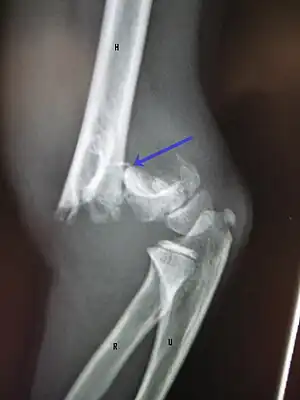

Distal humerus fractures usually occur as a result of physical trauma to the elbow region. If the elbow is bent during the trauma, then the olecranon is driven upward, producing a T- or Y-shaped fracture or displacing one of the condyles.[7]

Definitive diagnosis of humerus fractures is typically made through radiographic imaging. For proximal fractures, X-rays can be taken from a scapular anteroposterior (AP) view, which takes an image of the front of the shoulder region from an angle, a scapular Y view, which takes an image of the back of the shoulder region from an angle, and an axillar lateral view, which has the patient lie on his or her back, lift the bottom half of the arm up to the side, and have an image taken of the axilla region underneath the shoulder.[9] Fractures of the humerus shaft are usually correctly identified with radiographic images taken from the AP and lateral viewpoints.[12] Damage to the radial nerve from a shaft fracture can be identified by an inability to bend the hand backwards or by decreased sensation in the back of the hand.[5] Images of the distal region are often of poor quality due to the patient being unable to extend the elbow because of pain. If a severe distal fracture is suspected, then a computed tomography (CT) scan can provide greater detail of the fracture. Nondisplaced distal fractures may not be directly visible; they may only be visible due to fat being displaced because of internal bleeding in the elbow.[7]